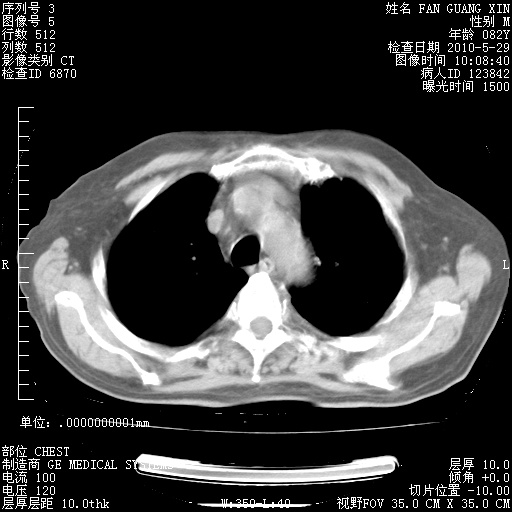

还需要哪些辅助检查?我们医院排除真菌感染没有任何检验方法,胸片好像能够排除肺部真菌感染。

补充:ENA化验全部阴性。免疫五项(IgG、IgA、IgM、C3、C4)只有C4略高。

CD3+ T细胞/淋巴细胞 46% (参考值50.00~84.00%)

CD3+CD4+ T细胞/淋巴细胞 21% (参考值27.00~51.00%)

CD3+CD8+ T细胞/淋巴细胞 25% (参考值15.00~44.00%)

CD3+CD4+ T细胞/CD3+CD8+ T细胞 0.84 (参考值0.71~2.78)

T细胞亚群是治疗5天采血。